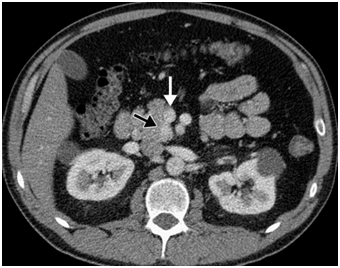

The latest studies have demonstrated that MRI is superior to other preoperative imaging techniques in identifying small pancreatic insulinoma. Its sensitivity ranges from 85% to 95%, in the detection of insulinoma and the determination of the presence of metastases. Using conventional sequences, small insulinoma usually have a low signal on T1-weighted sequences and a high signal on T2-weighted sequences. Some insulinomas containing fibrous tissue may show low signal intensity on both T1- and T2-weighted images. An improvement in MRI technique is the use of diffusion weighted MRI (DWI-MRI) for abdominal imaging. DWI is an MRI technique that detects changes in the molecular diffusion of water in biologic tissues and the valuable role of DWI in the detection of pancreatic tumors has been reported in several studies (Figure 4A), (Figure 4B) & (Figure 5).33–36

Figure 4 Localization of a possible insulinoma in the case patient. (a) CT scan of the abdomen of the patient described showing nodular pancreas but no differential enhancement after contrast (b) | MRI scan of the abdomen showing a 18.3mm by 9.5mm enhancing islet cell tumor within the tail of the pancreas. 31

Figure 5 Example of the use of MRI in the localisation of insulinoma. (a) T2-weighted image demonstrating a lesion in the tail of the pancreas, less well seen in (b) T1-weighted MRI demonstrating the pancreas in the same patient. 32